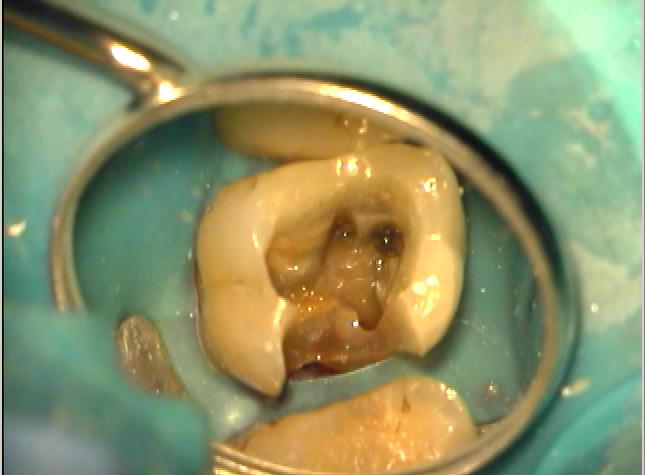

Klinische Situation nach abgeschlossener Aufbereitung

Vergrößerte Situation

Vergrößerte Situation; deutlich sind die 4 Kanaleingänge zu erkennen